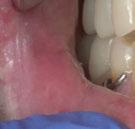

–Implante inmediato en incisivo lateral superior con técnica de «Socket Shield» y acceso vestibular para legrado de la lesión periapical, por el Dr. Ignacio Tormo Jiménez y cols. [106]